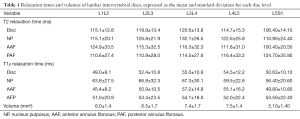

Table 1 shows the values of relaxometry for each lumbar disc. The cranial and caudal segments of the lumbar spine, namely L1L2 and L5S1, respectively, had the lowest relaxation time values, while the highest values were observed for the L3L4 central disc segments. A similar trend was observed for the IVD volumes. The average relaxation times for men were T2 =116.0±15.9 ms and T1ρ =51.6±9.1 ms; for women, T2 =114.7±13.7 ms and T1ρ =52.9±12.2 ms. There was no significant difference between men and women for either relaxometry map (T2, P=0.37; T1ρ, P=0.97). The relaxation times of the NP were higher than the anterior and PAF both T2 (Kruskal-Wallis =37.37; P<0.0001) and T1ρ (Kruskal-Wallis =45.49; P<0.0001). In T2 relaxometry there was no difference between the anterior and posterior annulus, however, in the AAF T1ρ relaxometry values were higher than the PAF (Table 2).

Full table

Full table

As shown in Table 4, we observed a negative linear correlation between T2 relaxation times and age at all lumbar disc levels (P<0.02 at all levels). There was no correlation between age and volumetry for any disc (P>0.07 at all levels). We also observed no relationship between age and T1ρ values for any disc level (P>0.06 at all levels). BMI, height and weight were not correlated with any lumbar IVD relaxometry measurement.

The stratification of the IVD into NP, AAF and AAF made possible to analyze separately the correlation of each sub-region with ageing (Figure 6). Table 2 shows the correlation values (r) for each disc sub-region (NP, and PAF AAF) at each disc level (L1L2 to L5S1). T2 relaxation times of NP and PAF correlate negatively with aging at all disc levels, except for the sub-region PAF in L5S1 disc. T1ρ relaxometry correlates only with the sub-region NP of L1L2 and L3L4 IVDs.